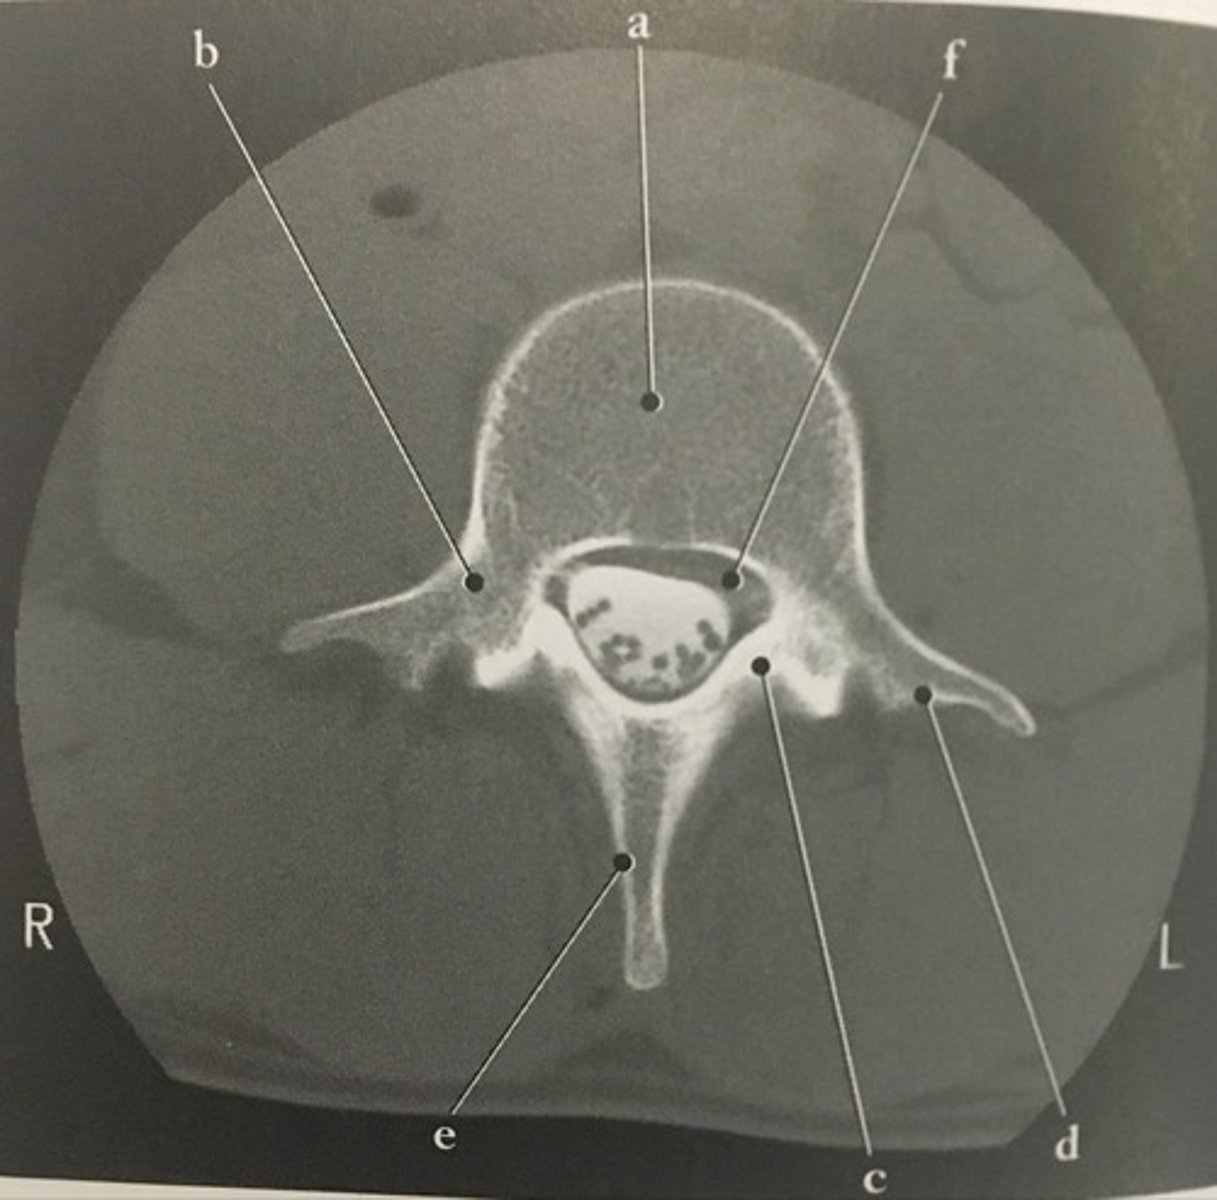

Body

Identify structure A on this axial CT slice of the lumbar vertebra.

<p>Identify structure A on this axial CT slice of the lumbar vertebra.</p>

93

New cards

Pedicle

Identify structure B on this axial CT slice of the lumbar vertebra.

<p>Identify structure B on this axial CT slice of the lumbar vertebra.</p>

94

Lamina

Identify structure C on this axial CT slice of the lumbar vertebra.

<p>Identify structure C on this axial CT slice of the lumbar vertebra.</p>

95

Transverse process

Identify structure D on this axial CT slice of the lumbar vertebra.

<p>Identify structure D on this axial CT slice of the lumbar vertebra.</p>

96

Posterior spinous process

Identify structure E on this axial CT slice of the lumbar vertebra.

<p>Identify structure E on this axial CT slice of the lumbar vertebra.</p>

97

Vertebral foramen

Identify structure F on this axial CT slice of the lumbar vertebra.

<p>Identify structure F on this axial CT slice of the lumbar vertebra.</p>